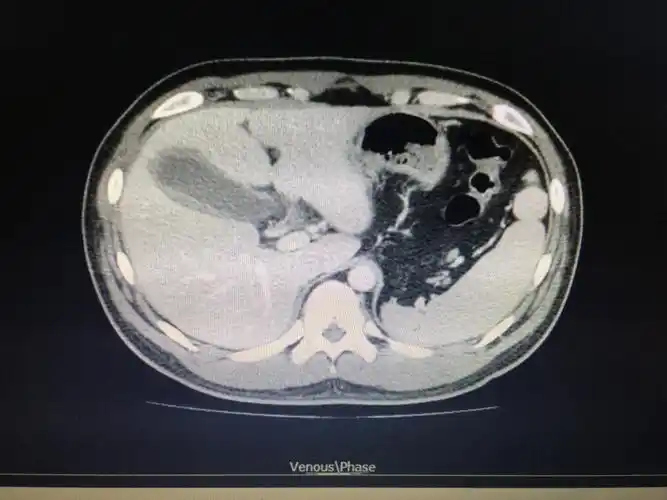

ct胆囊炎,未见结石.